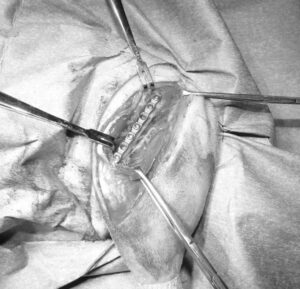

大腿骨骨折のフェレットちゃんの手術依頼でご紹介がありました。TAITAN1.2プレートを使用し無事歩けるようになりました。よかったね。